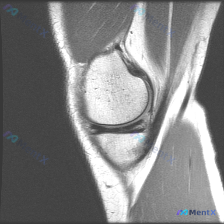

遇到一个挺典型的「临床-影像不匹配」的病例,整理出来和大家聊聊思路。 病例核心信息 问题:临床怀疑存在半月板异常,仅提供单张膝关节MRI-T2序列矢状位影像,请给出影像判断和分析。 影像所见整理 这张影像的情况是: 1. 骨结构:股骨远端、胫骨近端、髌骨皮质轮廓完整,骨髓信号均匀,没有骨折、骨挫伤、...

看到一个有意思的读片病例,整理一下资料和分析思路,跟大家分享一下。 病例基本信息 核心问题:患者主诉怀疑「半月板异常」,提供一张膝关节矢状位T2加权MRI图像,要求分析影像表现。 影像学读片结果 我们先逐结构捋一遍: 1. 图像质量:这是标准的矢状位T2加权图像,解剖结构清晰,对比度好,没有明显运动...

拿到这份病例和影像,先整理一下所有信息,再梳理思路: 一、核心临床问题 本次提出的核心疑问是:判断是否存在半月板异常 二、现有影像学发现(膝关节MRI T2序列冠状位单层面) 我先把所有客观发现整理出来: 1. 骨骼与关节软骨:股骨远端、胫骨近端骨皮质连续,无骨折;骨髓信号均匀,无明显水肿/硬化;关...

看到一份膝关节MRI的读片需求,核心问题是半月板异常,我整理了完整的分析思路,分享给大家。 病例影像基础信息 这是一张膝关节矢状位T2加权MRI,观察层面为膝关节外侧室,可显示股骨外侧髁、胫骨外侧平台、外侧半月板体部结构。 系统性影像学发现 1. 骨骼与关节软骨:股骨、胫骨骨皮质信号正常,骨髓无异常...